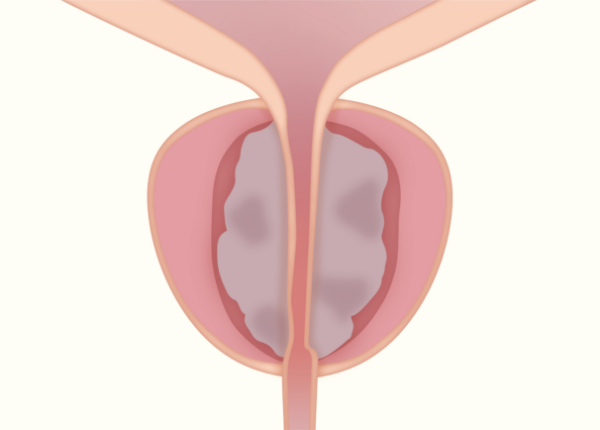

前立腺肥大症とは

前立腺肥大症は加齢とともに増加し、80歳以上では80%を超えると言われています。

肥大した前立腺が尿道を圧迫すると、尿の出が悪くなったり、日中や夜間の排尿回数が増えるなどの症状が出現し、重度の前立腺肥大症では、自力で排尿がまったくできなくなってしまう尿閉と呼ばれる状態になることもあります。

RezumシステムによるWAVE治療は、水蒸気を用いた前立腺肥大症に対する治療で低侵襲かつ異物を体内に残さずに治療することが可能になります。